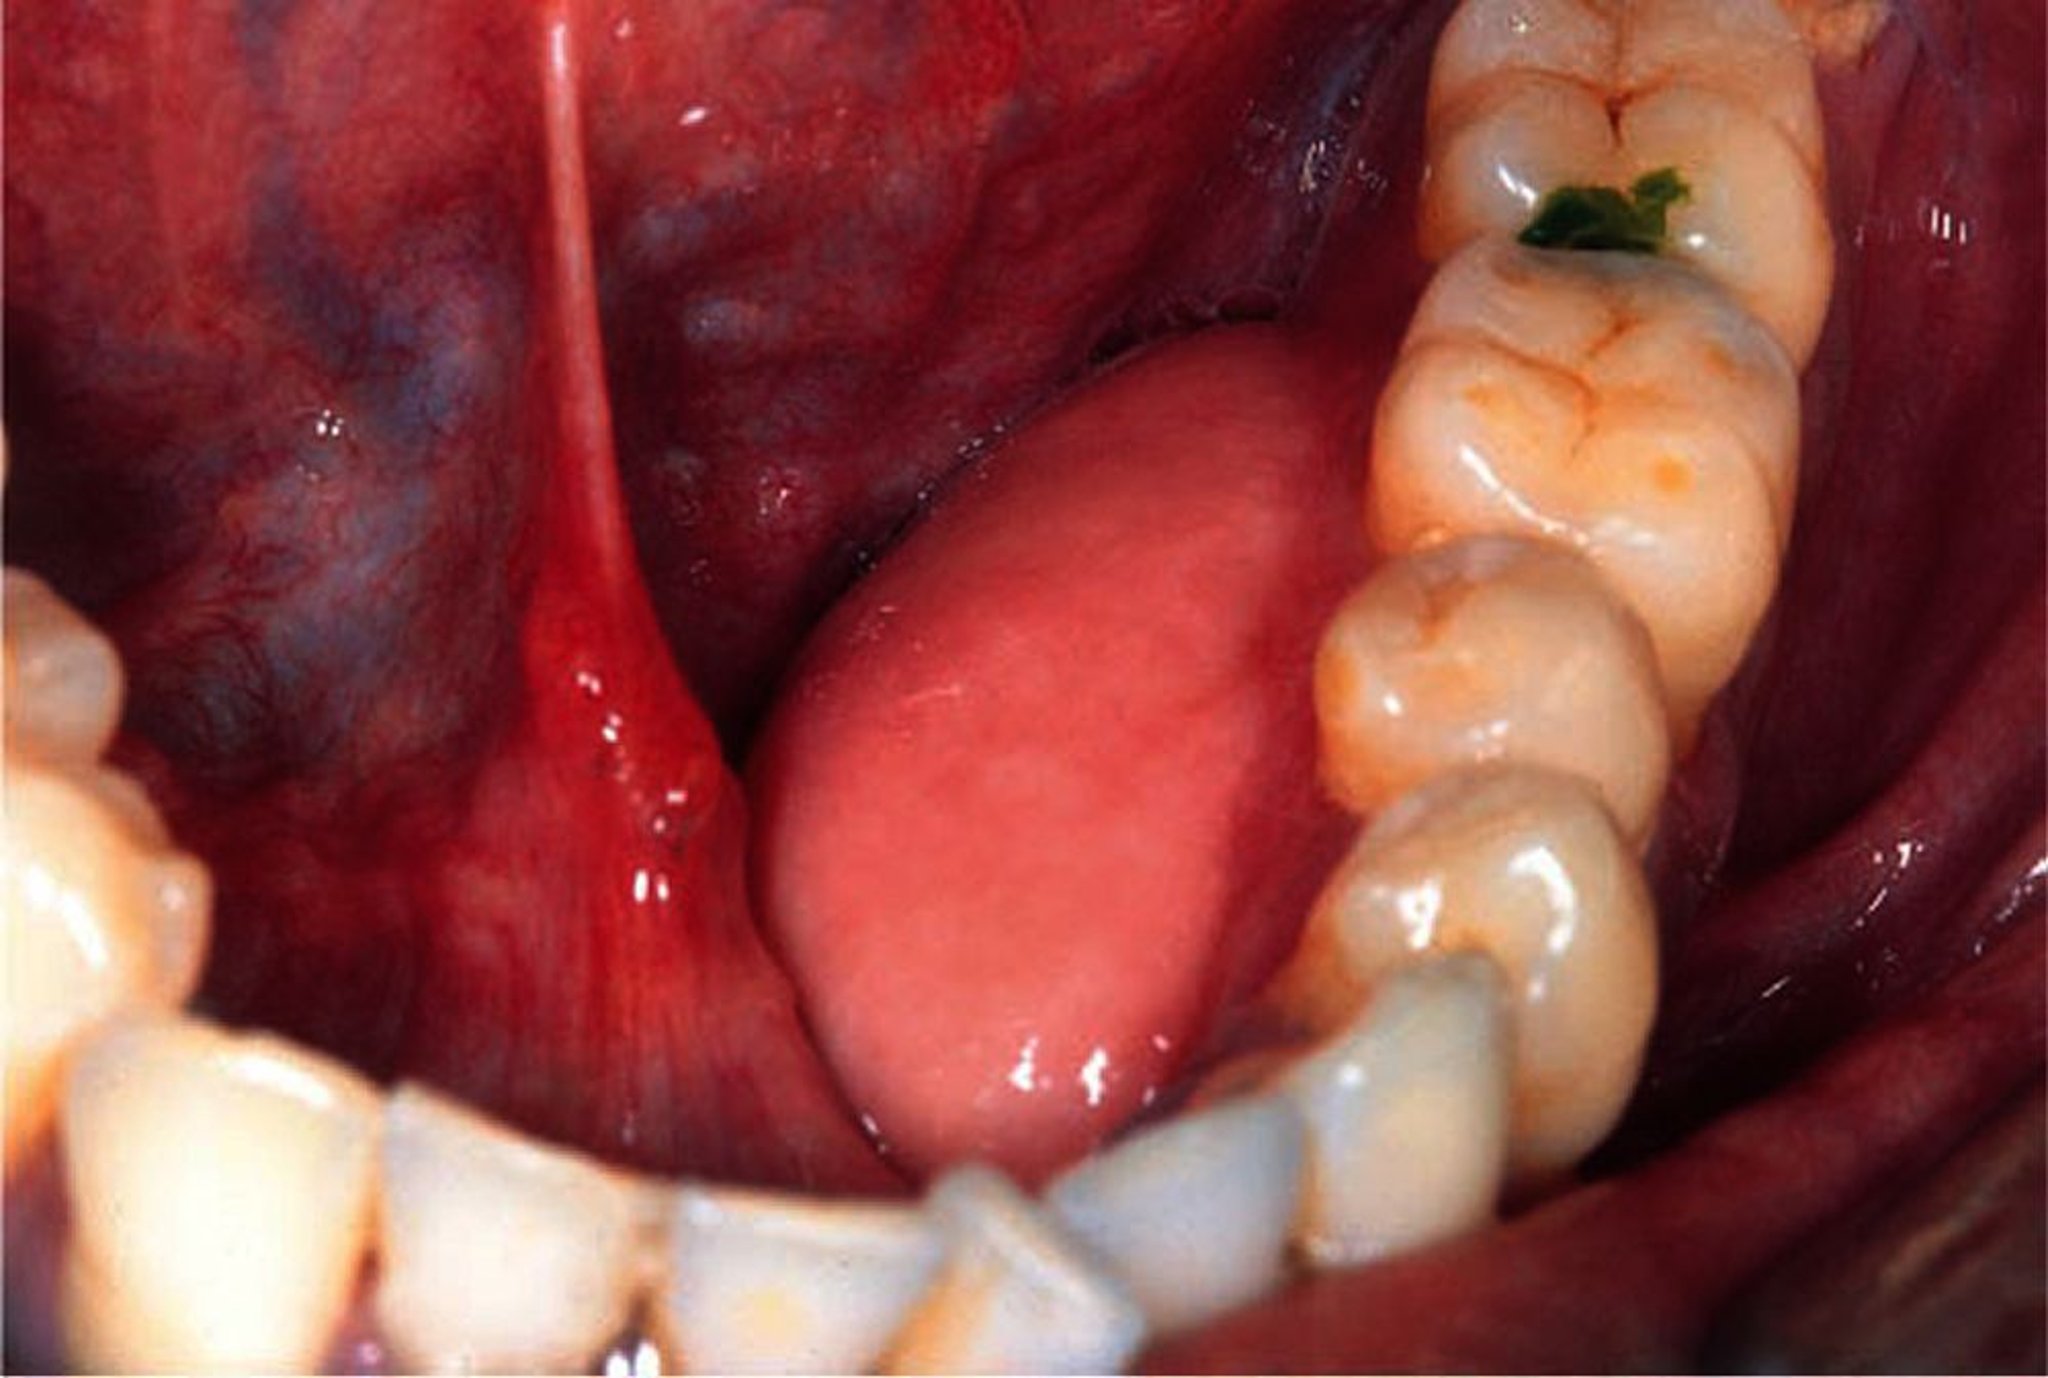

Torus mandibulaire

Une excroissance bénigne de la face linguale de la mandibule est visible ici sur le côté gauche de la bouche du patient.